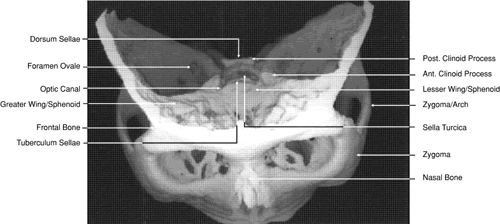

The globe is shown in Figure 12. The orbit and periorbital structures are shown in Figures 13 through 16, and the optic canal is shown in Figures 17 through 26. The cavernous sinus and optic chiasm are shown in Figures 27 and 28, and the posterior visual pathway and cranial nerves are shown in Figures 29 through 33.

Fig. 29. A. Axial computed tomography soft tissue image at the level of the base of skull. B. Axial computed tomography bone window image at the level of the base of skull.